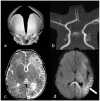

Timothy syndrome (TS) is an autosomal dominant condition with the constellation of features including prolonged QT interval, hand and foot abnormalities, and mental retardation or autism. Splawski et al. [2004] previously described two phenotypes associated with TS distinguished by two unique and different mutations within the CACNA1C gene. We report on a newborn who presented with prolonged QT interval and associated polymorphic ventricular tachycardia, dysmorphic facial features, syndactyly of the hands and feet, and joint contractures, suggestive of TS. He developed a stroke, subsequent intractable seizures, and was found to have cortical blindness and later profound developmental delay. Initial targeted mutation analysis did not identify either of the previously described TS associated mutations; however, full gene sequencing detected a novel CACNA1C gene mutation (p.Ala1473Gly). The clinical and genetic findings in our case expand both the clinical and molecular knowledge of TS.